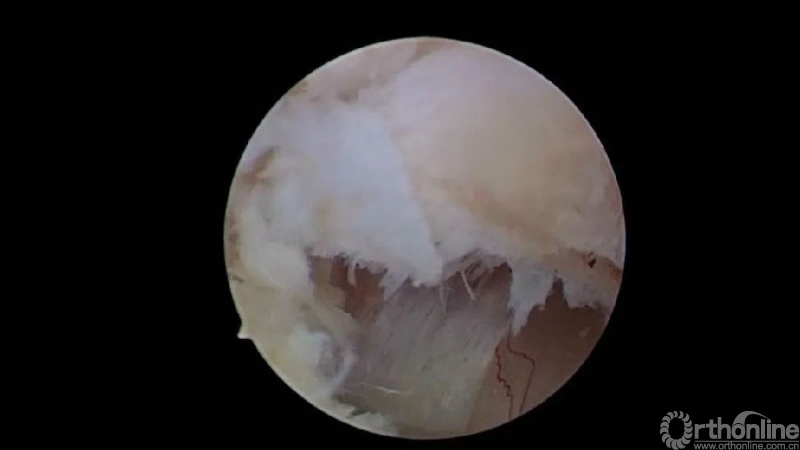

UBE ULBD对侧黄韧带与硬膜之间的间隙较小的病例,可沿黄韧带的四周游离。去除浅层后,于对侧的关节突关节方向向下剥离深层黄韧带直至显露出上关节突的内缘及对侧的corner,枪钳处理松解对侧黄韧带的外缘。

沿下位椎体的棘突基底部及对侧椎板上缘剥离对侧黄韧带的远端止点,有些病例黄韧带的深层要覆盖于下位椎体椎板上缘的下方。使用剥离子将其剥离,对侧近端的黄韧带止点最容易剥离。